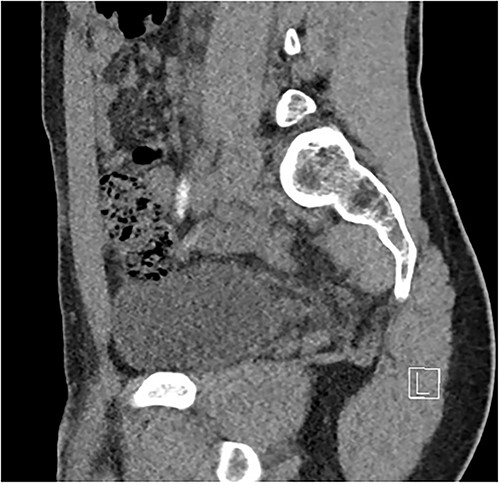

Two days following stent removal, the patient developed acute onset right lower quadrant and flank pain. A non-contrast CT of the renal tract was obtained to assess for procedure or stone-related complications. The scan demonstrated two distinct retained stones within the proximal right ureter, with associated moderate ureteronephrosis. Additionally, within the right lower quadrant of the abdomen, a radiopaque vermiform entity was demonstrated (Figs 1–3). This entity was not pathological, however, represented a normal appendix that had, consequent to contrast administration during a urological procedure, become filled with contrast secondary to vicarious contrast excretion.

Sagittal imaging, depicting the base of structure arising from the caecum.